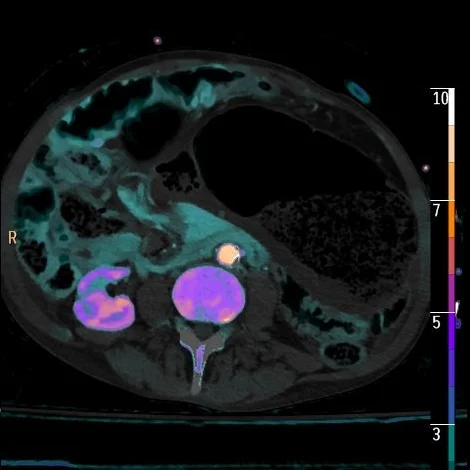

Iodine density overlay with no perfusion in wall of cecum and terminal ileum

Dilated segment of colon extends into pelvis, note absent perfusion in the wall on overlay image